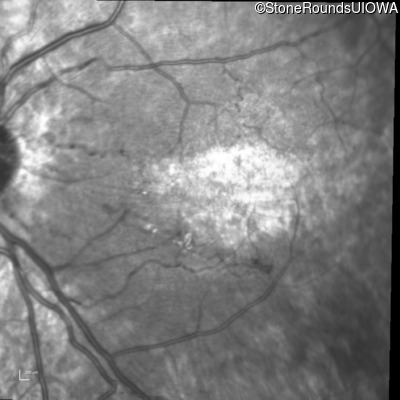

Infrared Fundus Photograph - Right - 20/160

Exemplar

Infrared Fundus Photograph - Left - 20/80 -1